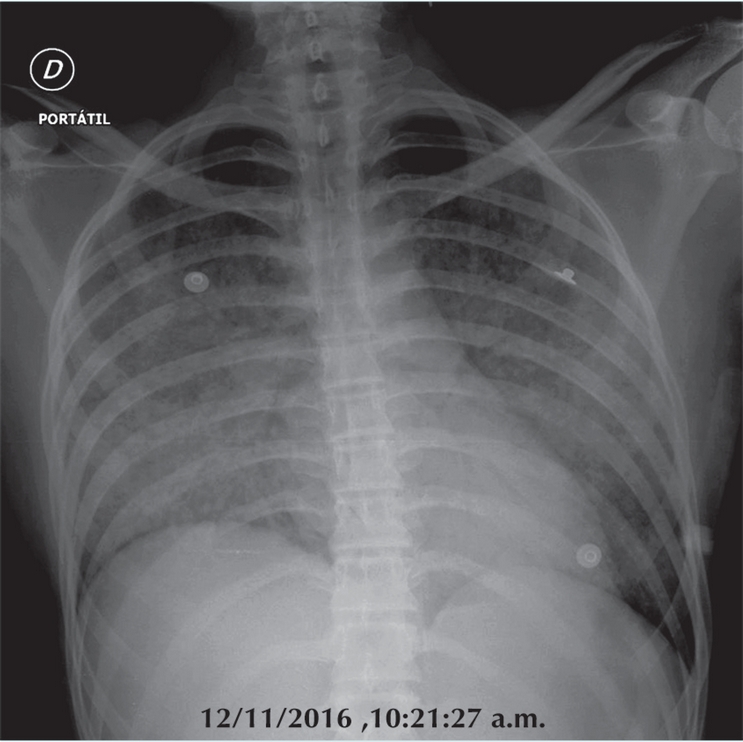

Ocho días después, el 12 de noviembre, se presentó en el Servicio de Urgencias hipotensa y con extremidades frías. Había empezado cuatro días antes con un cuadro de evacuaciones diarreicas, sin fiebre, dolor, náusea o vómito, que evolucionó a disnea y polipnea. Se recibió hipotensa (92/63 mm/Hg), taquicárdica (160 latidos por minuto), con polipnea (38 respiraciones por minuto) con desequilibrio hidroelectrolítico y acidosis metabólica (pH 7.17, PCO2 33.31 mm/Hg, HCO3 12mmol/L, Sat O2 32.7%, BE -15.2mmol/L, glucosa 143 mg/dL, lactado 4.18 mmol/L) y datos clínicos de choque. Tras varios intentos de venoclisis y osteoclisis se logró colocar venoclisis en yugular izquierda con colocación de catéter de presión venosa central, con mejoría parcial de la sintomatología. La radiografía de tórax mostró un neumotórax derecho a tensión y se aplicó un sello pleural. Siguió con deterioro electrolítico, presentaba acidosis metabólica e hiperlactatemia y luego deterioro ventilatorio y hemodinámico hasta el paro cardiorrespiratorio. Falleció a las 18:39 horas del mismo día 12 de noviembre.

Con el tratamiento instituido, la niña entró en remisión y desparecieron la masa mediastinal y los datos de afección mamaria (Figura 5). La autopsia aclara el cuadro final con una complicación pulmonar por Toxoplasma gondii; es una complicación rara de la inmunosupresión; sin embargo, de los parásitos intracelulares es el más usual. Se describe en el paciente inmuno comprometido con opacidades nodulares gruesas o con un patrón retículo nodular grueso, difuso, como el presentado finalmente por nuestra paciente, con una progresión rápida (Figura 6).